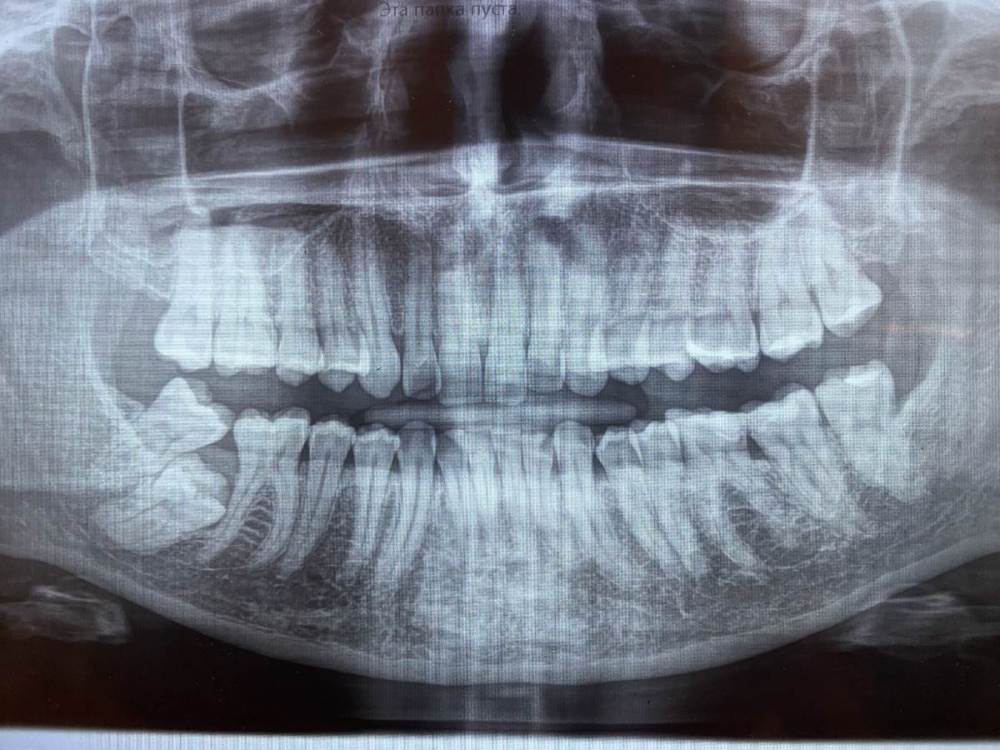

sparklemal Опубликовано 23 мая, 2021 Поделиться Опубликовано 23 мая, 2021 (изменено) доброе время суток всем, уважаемые хихурги, подскажите ваши варианты решения вопроса с застрявшей 7кой? КТ еще не делали, нечаянно недавно обнаружили на снимке 7ку. После снимка делали чистку, не помню как называется, которая под деснами прям и врач сказала что при надавливании на место между 6 и 8 выходил хлопьями гной, как бы старый уже, она чем-то промыла там как смогла. До чистки ничего не беспокоило. Ну и собственно, посоветуйте хирурга )) город Москва. Изменено 23 мая, 2021 пользователем sparklemal Ссылка на комментарий

Irouil Опубликовано 23 мая, 2021 Поделиться Опубликовано 23 мая, 2021 Нужно смотреть КТ, зайдите в ортодонтическую ветку, скорее всего 8ка подлежит удалению и 7-ка экструзии 1 Ссылка на комментарий